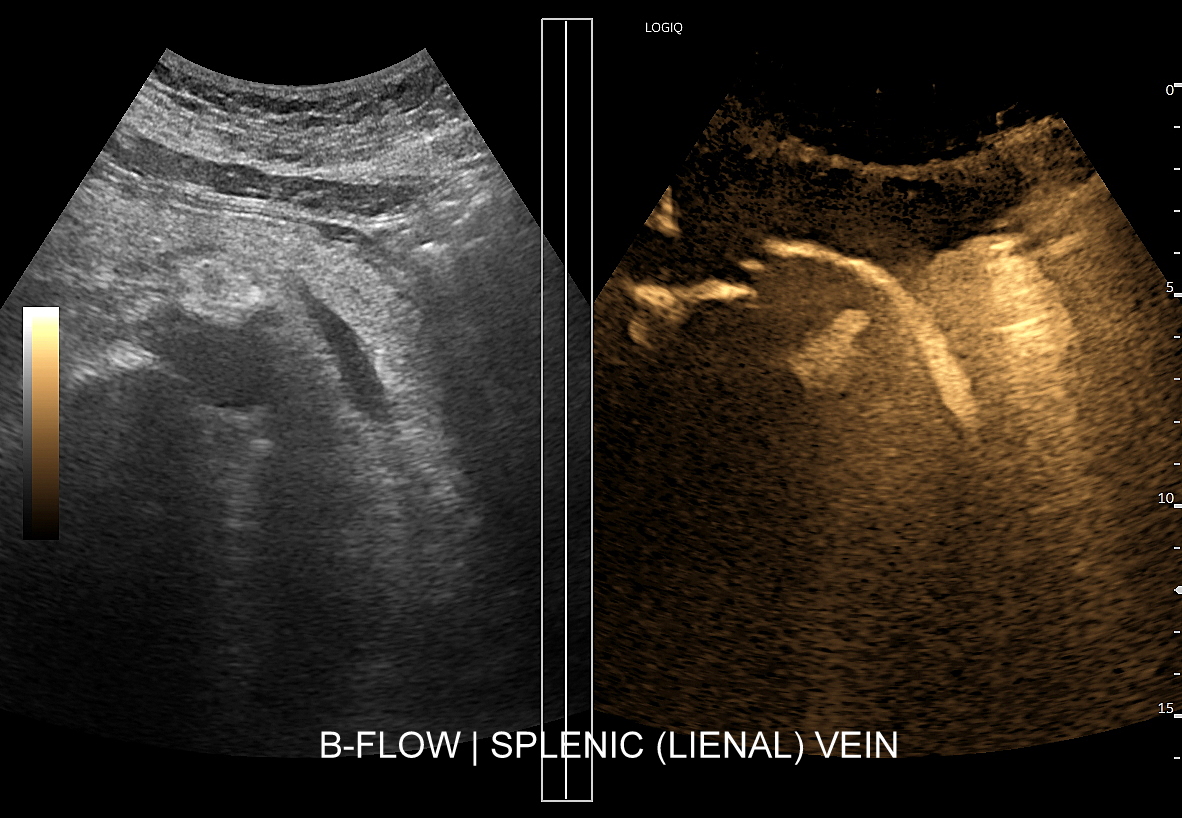

Tryb B-flow wyjątkowo korzystnie sprawdza się także przy badaniu wnętrza dużych i średnich naczyń. Otóż umożliwia on pewne zobrazowanie drożności naczynia, umożliwia wykazanie obecności / lokalizacji naczynia przy niesprzyjających warunkach obrazowania w trybie B, a poza tym uzyskiwane w omawianym trybie obrazy zarysów błony wewnętrznej naczyń (np. tętniczych blaszek miażdżycowych, skrzeplin przyściennych, zmian w przebiegu dysplazji włóknisto-mięśniowej, czy zapaleń tętnic) charakteryzują się wysoką rozdzielczością i kontrastowością. Skany dużych naczyń w trybie B-flow przypominają wręcz te uzyskiwane w klasycznej angiografii opartej o promieniowanie rentgenowskie. B-flow wykorzystywany może być praktycznie i rutynowo do obrazowania naczyń szyi i kończyn, naczyń wątroby, naczyń trzewnych, nerkowych oraz dużych naczyń brzusznych.